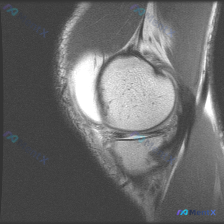

看到一个挺有意思的读片病例,其实更考验临床基本功,整理出来和大家分享一下。 病例基本信息 用户问题:询问这张影像上能看到什么半月板异常 提供的影像分析:这是一张肩关节MRI T2序列冠状位图像 影像可见表现: 1. 肱骨头与关节盂对位正常,肩峰形态可观察,未见明显骨髓水肿或骨质破坏 2. 冈上肌腱走...